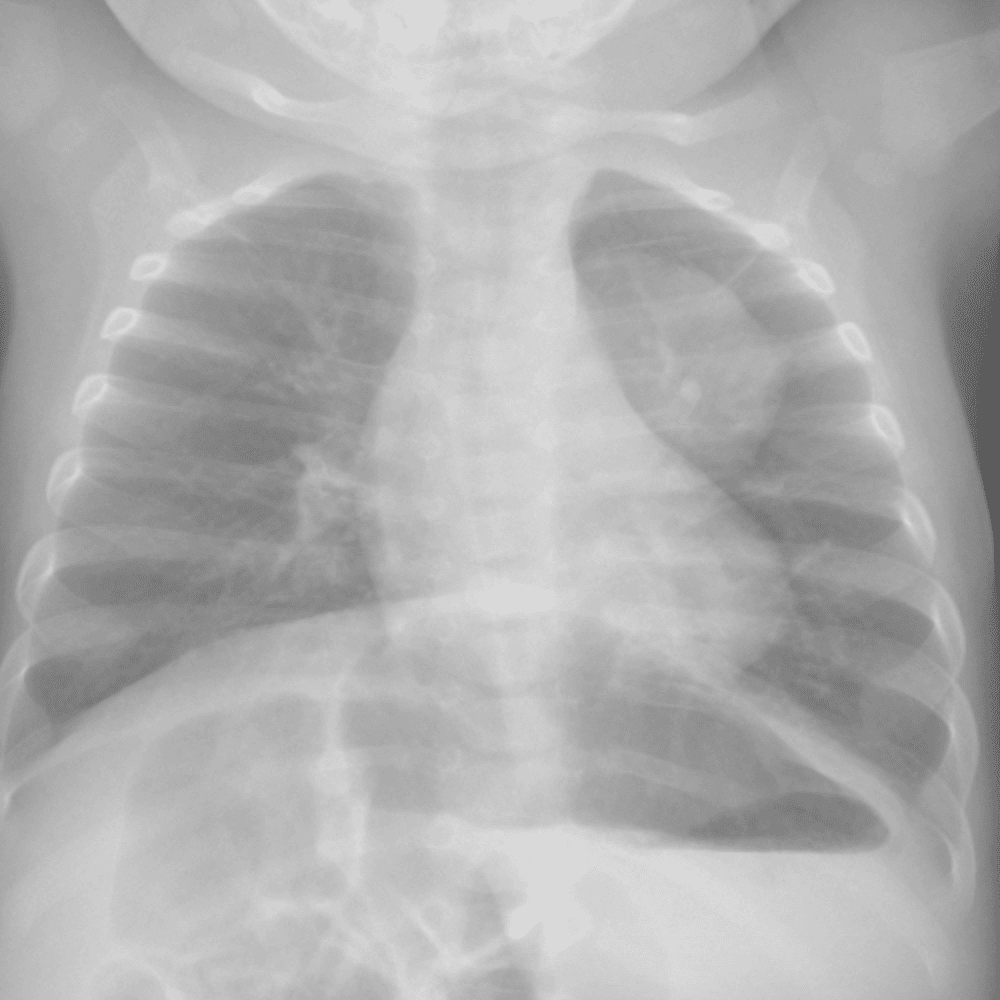

Peds Chest

Practice

Simulates call by including subtle or difficult cases and some normals.

50 cases